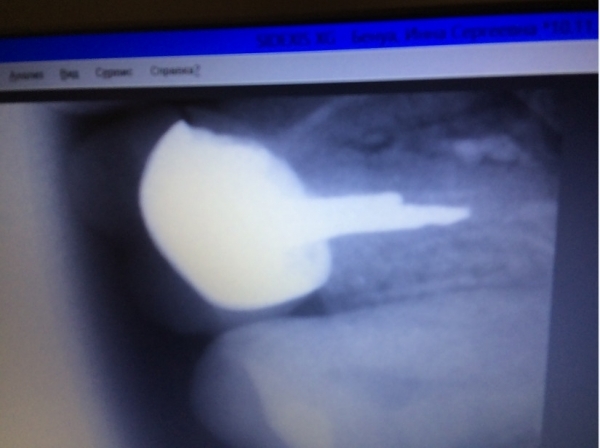

Сутки назад поставил коронку на живой зуб (жевательный снизу), до установки коронки зуб не болел. До установки пломба была большой и отвалилась часть стенки зуба, врач-стоматолог посмотрел снимок и сказал, что лучше ставить на живой зуб, так как воспалений и всяческих патологий нет, зуб лучше сохранить, коронка цирконий!

Такое случается, но острой боли быть не должно. Скорее всего, чувствительность не пройдет, а будет усиливаться, так как при обточке зуб уже реагировал на внешние факторы. Покажитесь врачу, сделайте рентген и картина будет ясна.